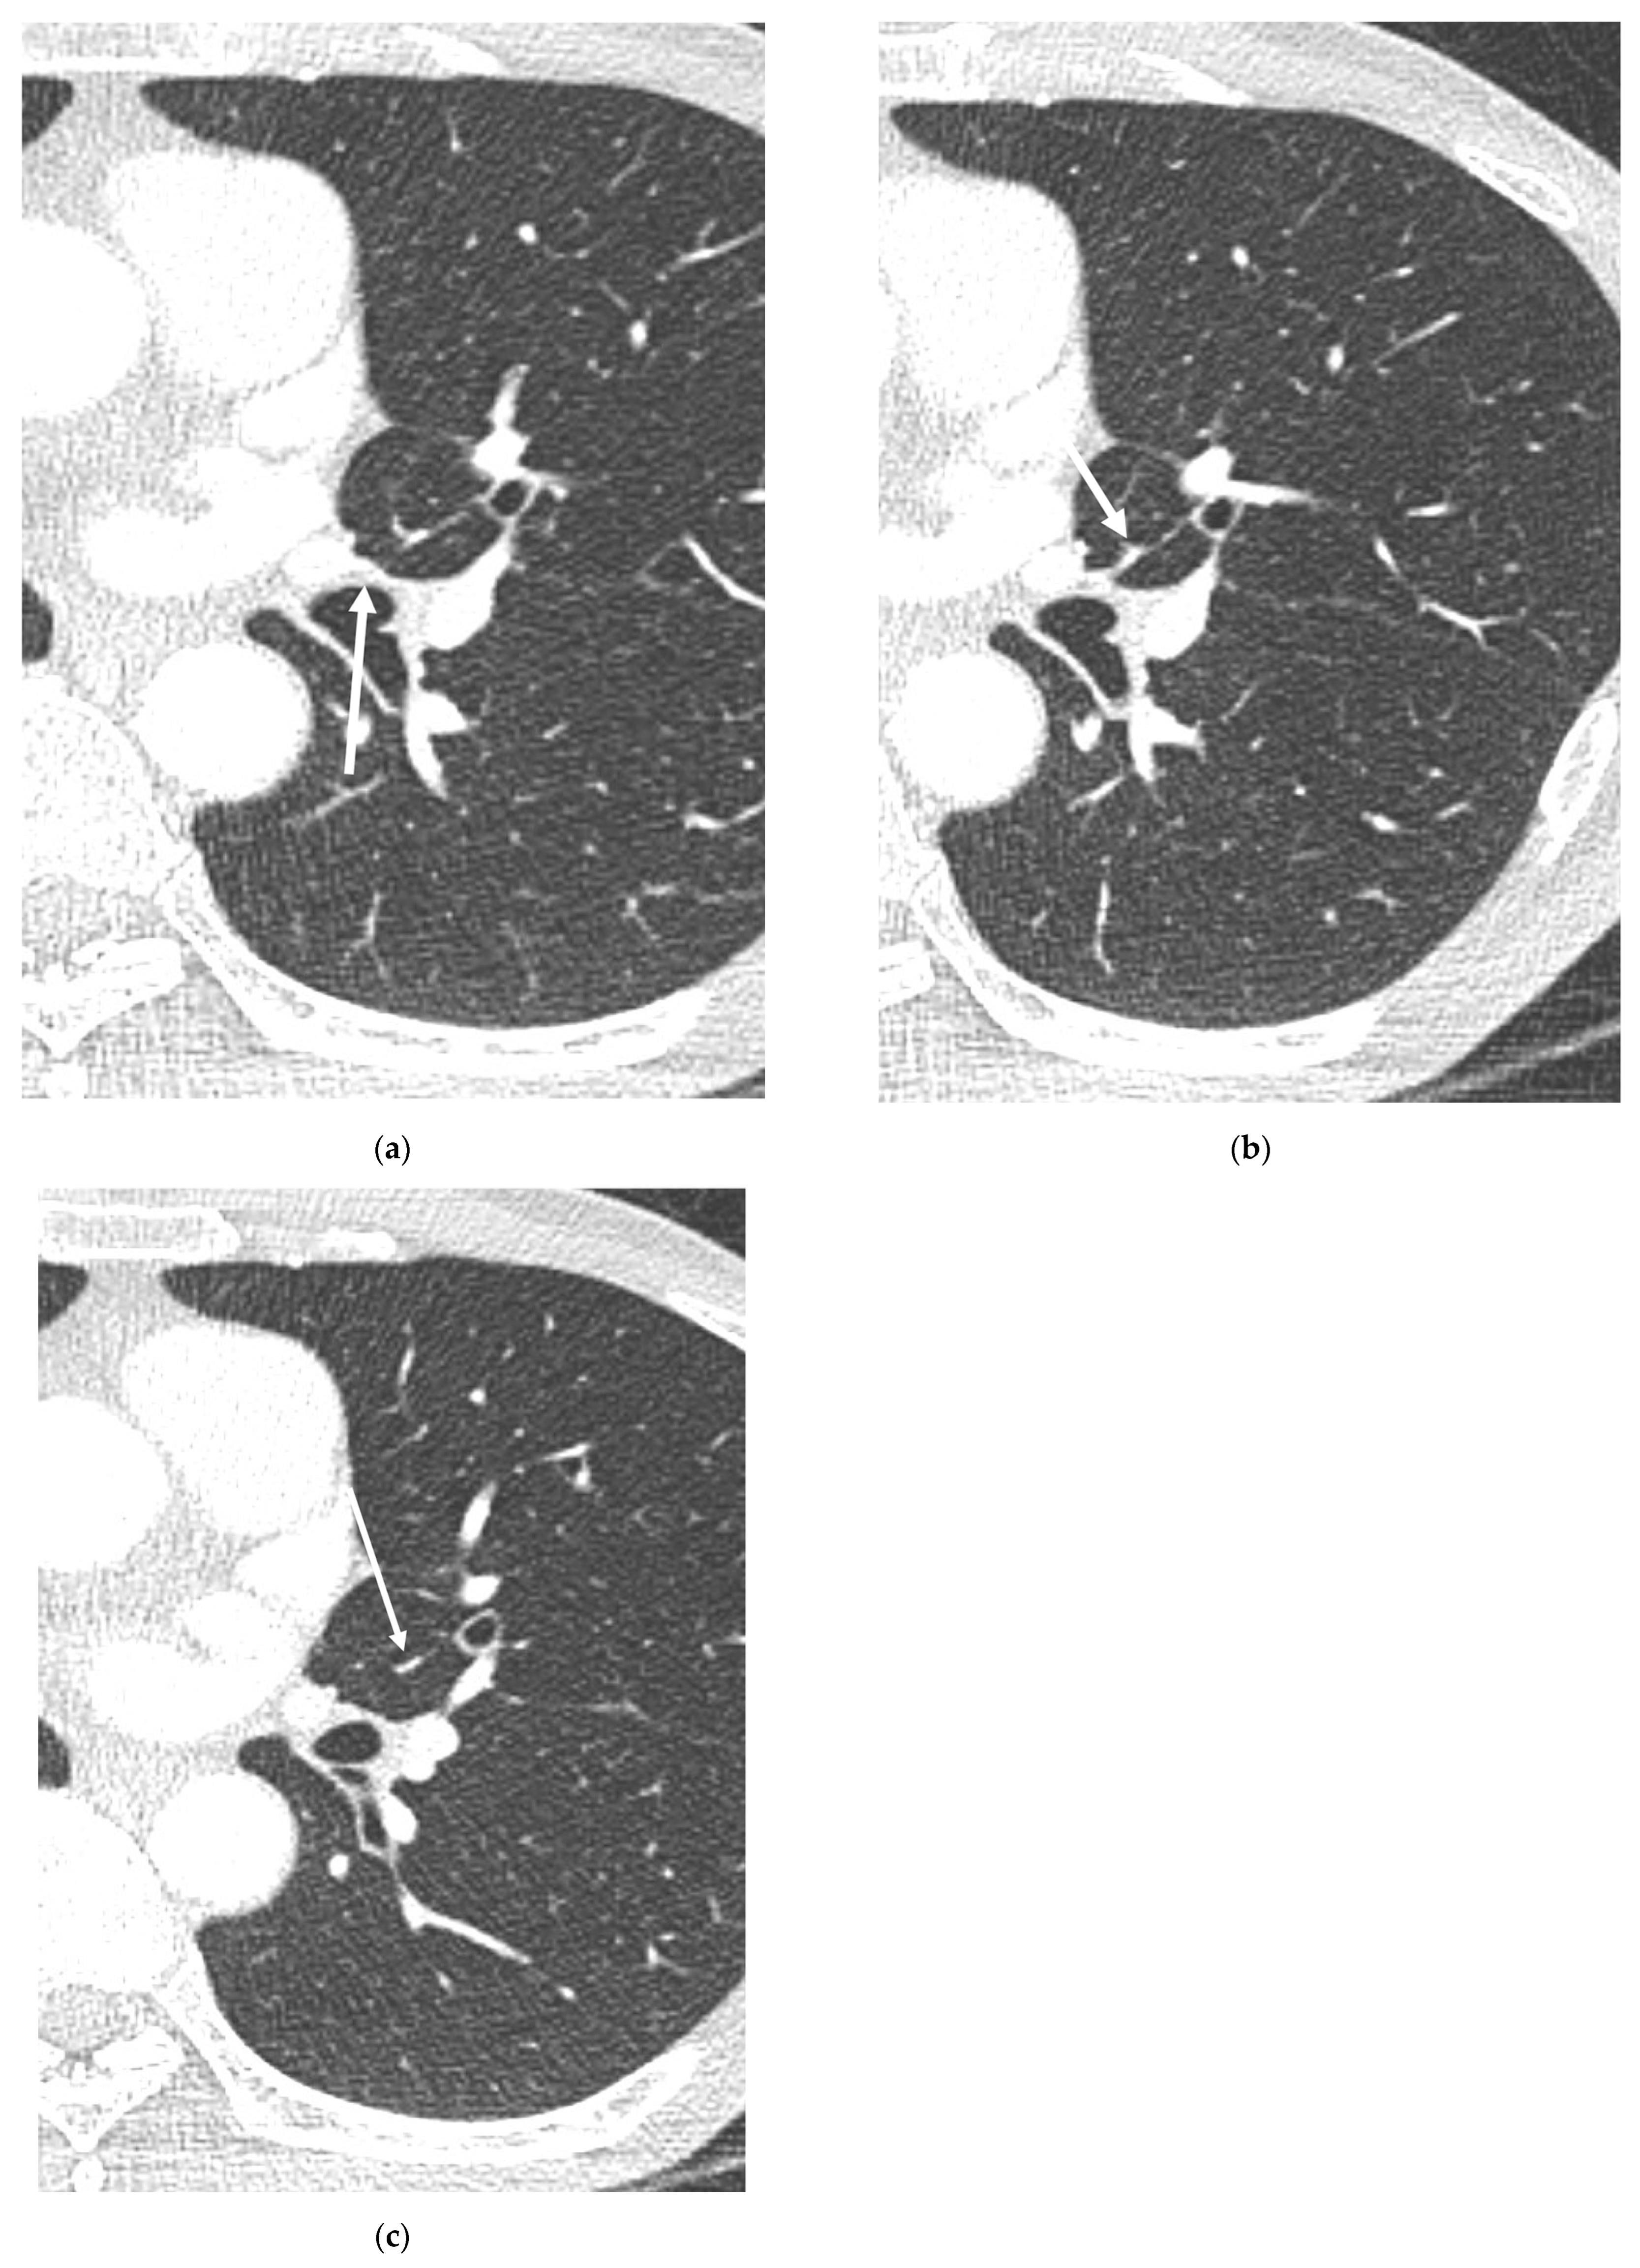

3. Results

3.2. Lobar and Segmental Supply Patternf of the AP

3.3. Diameter of the AP

4. Discussion